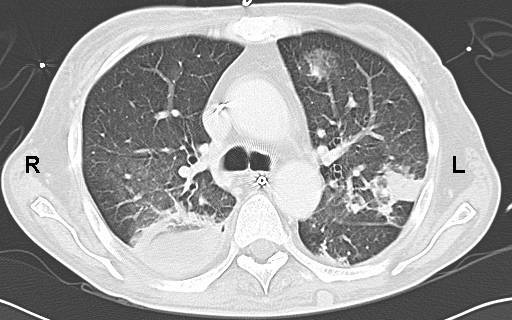

X ray - aspergilloma - opacity with a hole

When do you get invasive aspergillosis and what happens?

Immunocomprimised - rapidly takes over lungs and invades blood vessels